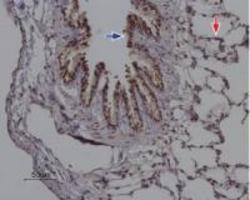

Immunohistochemistry

TA328751 IHC

Other validation